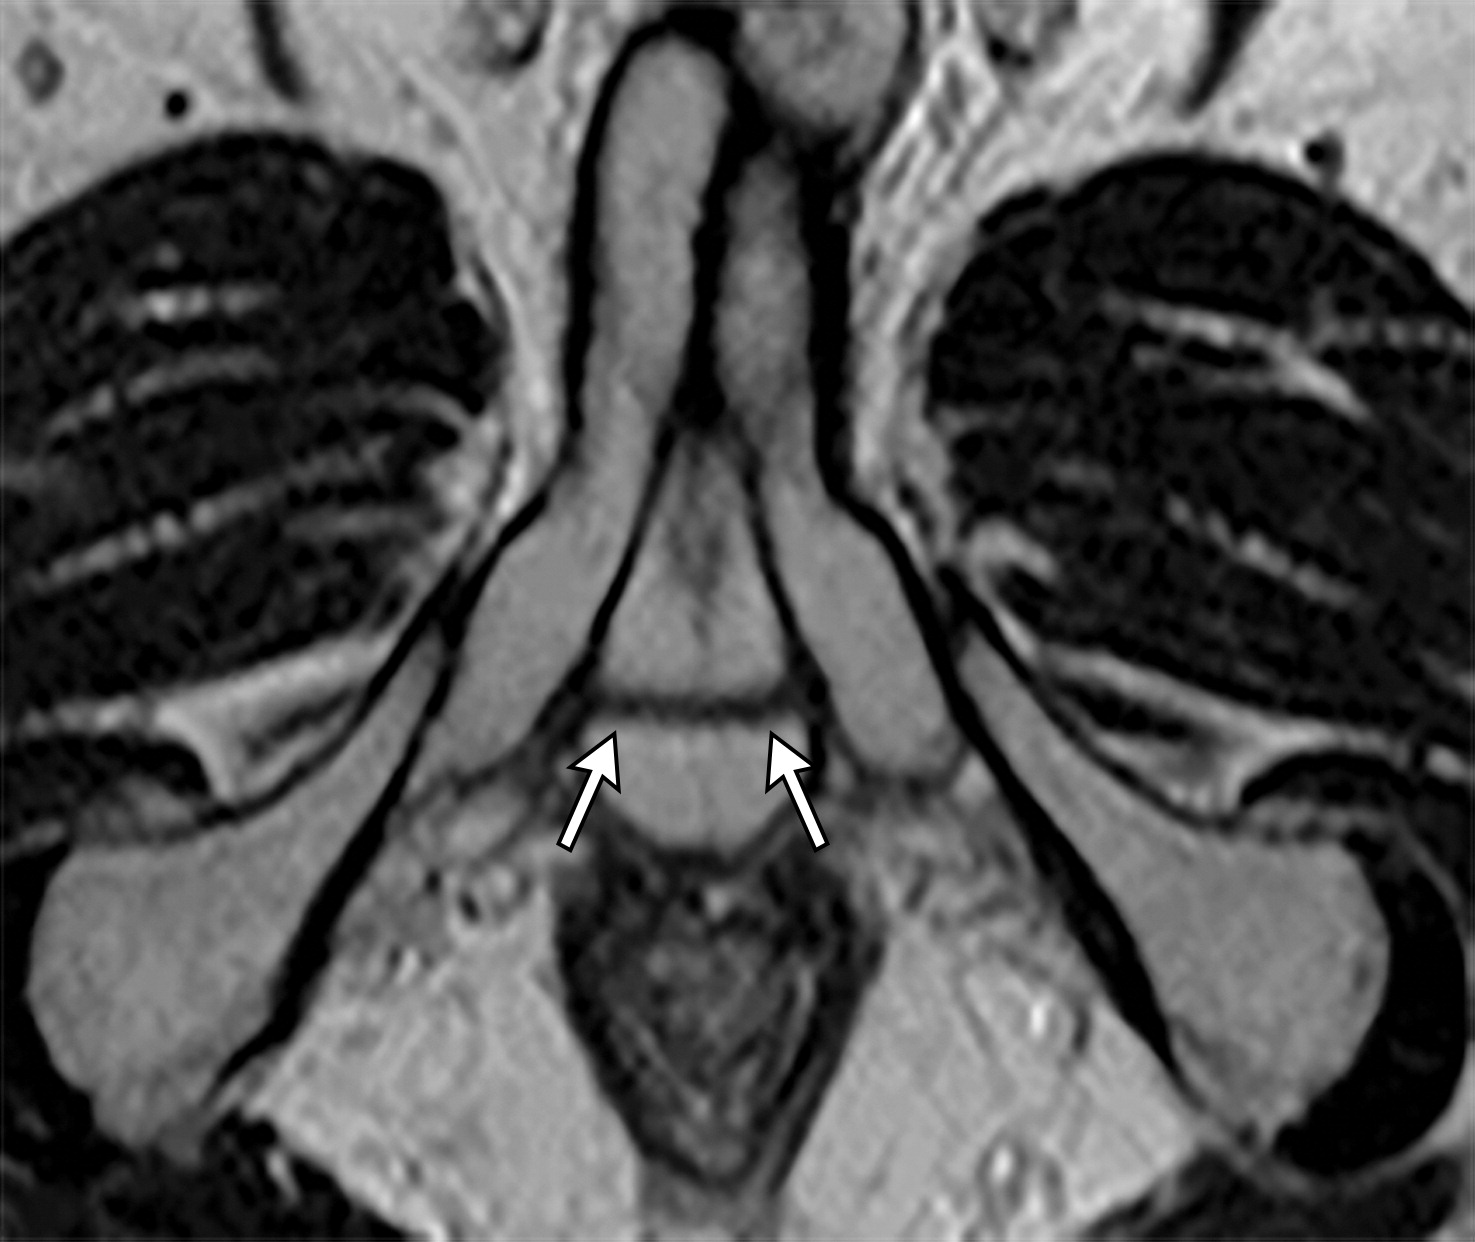

50岁以上男性骨盆和盆底的MRI解剖。

提肛肌(LA),由耻骨直肠肌(PR)、耻骨尾骨肌(PC)和髂尾骨肌(IC)组成;尾骨肌(C),前列腺(P),闭孔内肌(OI),会阴浅横肌(STP),球海绵体肌 (B), 坐骨海绵体肌(ISC),肛门外括约肌(EAS),肛门内括约肌(IAS),直肠(R),尿道括约肌(SU),也称为尿道外括约肌(U),它包围着整个膜性尿道。6774449af17bb1b8df6e83ab4e9fa158.jpeg